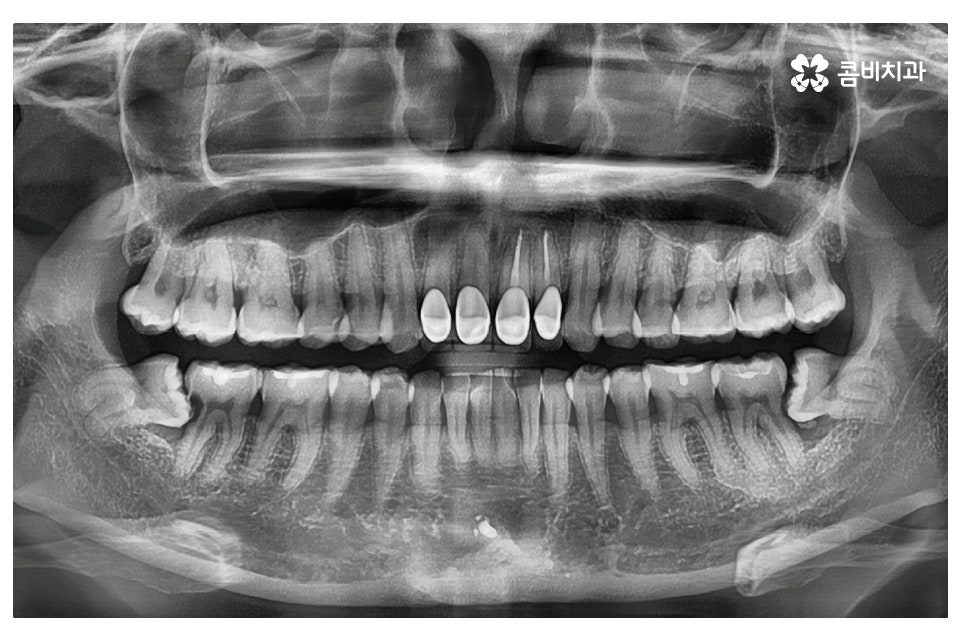

엑스레이 사진에서 보시는 것처럼 사랑니로 인해 어금니 옆 부분에

충치가 발생되었고 사랑니 발치 후 어금니 신경치료를 하여

자연치아의 손상이 커진 케이스라고 할 수 있는데요

오늘 보여드린 환자분의 케이스는 사랑니로 인해 어금니에도

충치가 발생한 사례로 이처럼 치아 사이에 충치가 발생하면

치아의 하단부, 안쪽에 손상이 발생하기 때문에

어금니 신경치료를 하게 되는 경우로 이어질 수 있어요.